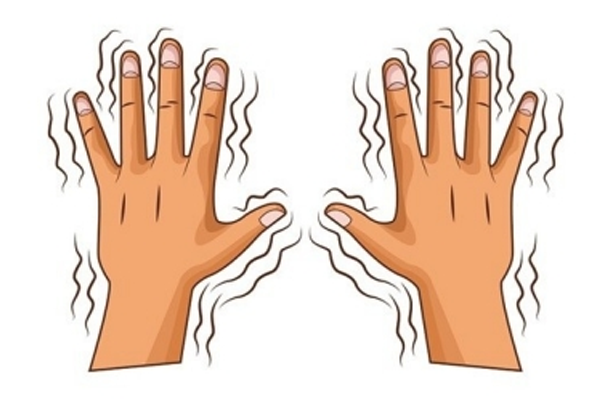

Parkinson’s disease is a progressive neurological disorder which leads to shaking (tremor), stiffness, slowness of daily activities, and difficulty with walking, balance, and coordination.

- Tremors at rest of hands, legs, and/or jaw